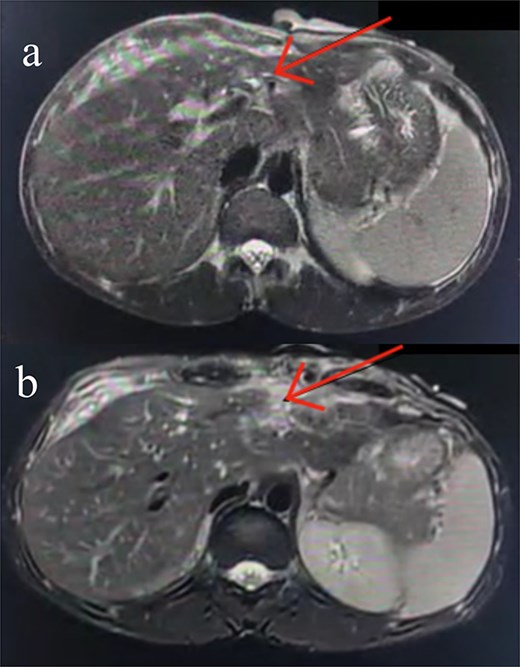

Seven days post-op, bile leakage from the surgical site raised suspicion of a biliary fistula. MRCP confirmed a hepatic parenchymal defect in communication with the biliary system and an external draining tract through the abdominal wall. A 6 × 1 cm subcapsular collection was also noted (Fig. 2).

A coronal MRCP image highlighting disruption at the level of the left intrahepatic biliary radicals, suggestive of a biliary leak. The discontinuity is evident at the confluence of the left hepatic duct (arrow), corresponding with the previously identified liver laceration. The extrahepatic biliary tree appears normal with no signs of obstruction or dilatation.